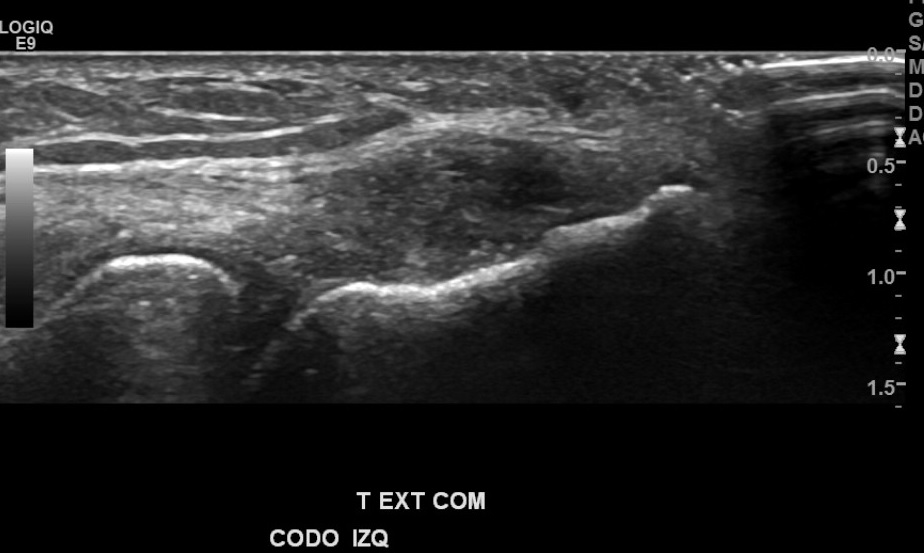

Antecedentes: chequeo por marcado dolor de región epicondilo lateral de codo izquierdo, mayor hace 1 mes aprox., por esfuerzo laboral de EESS, sin trauma.

Hallazgos: marcada heterogeneidad de tendón extensor común izquierdo, con foco de desgarro de espesor y ancho parcial en su espesor, con hiperemia al doppler color.